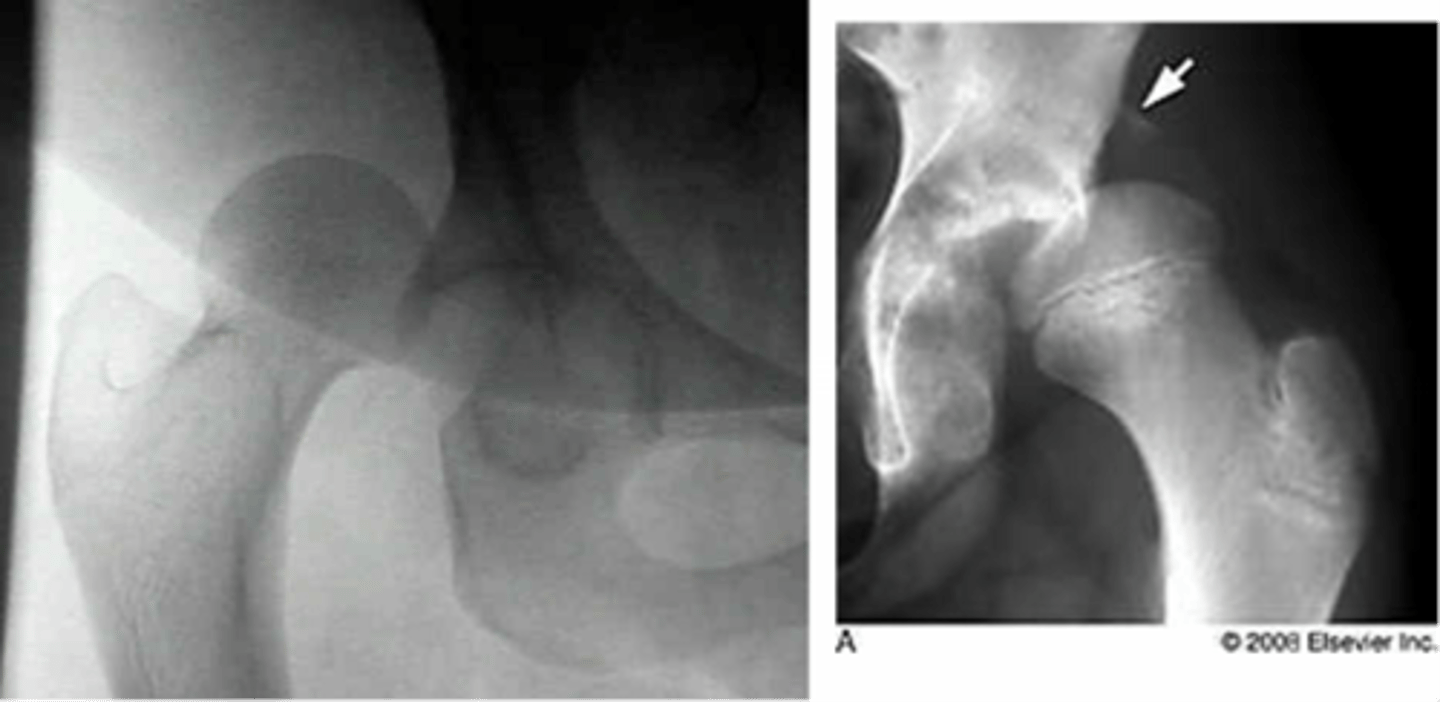

femoral acetabular impingement (FAI)

impingement between the femoral head/neck and acetabular rim

*occurs secondary to previous hip trauma/pathology with boney overgrowth (osteophytes)

TYPES:

1. cam

2. pincer

*most individuals have a combo of both

Cam type FAI

overgrowth of the femoral head/neck

Pincer type FAI

overgrowth of the acetabular rim